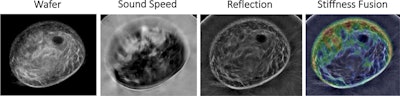

- Mammography vs. Ultrasound for Breast Tissue Analysis Mammography screening is one of the most recognized options for analyzing breast tissue in adult women. In contrast, the accuracy of this procedure allows it to be an alternative for women who cannot undergo mammography […]